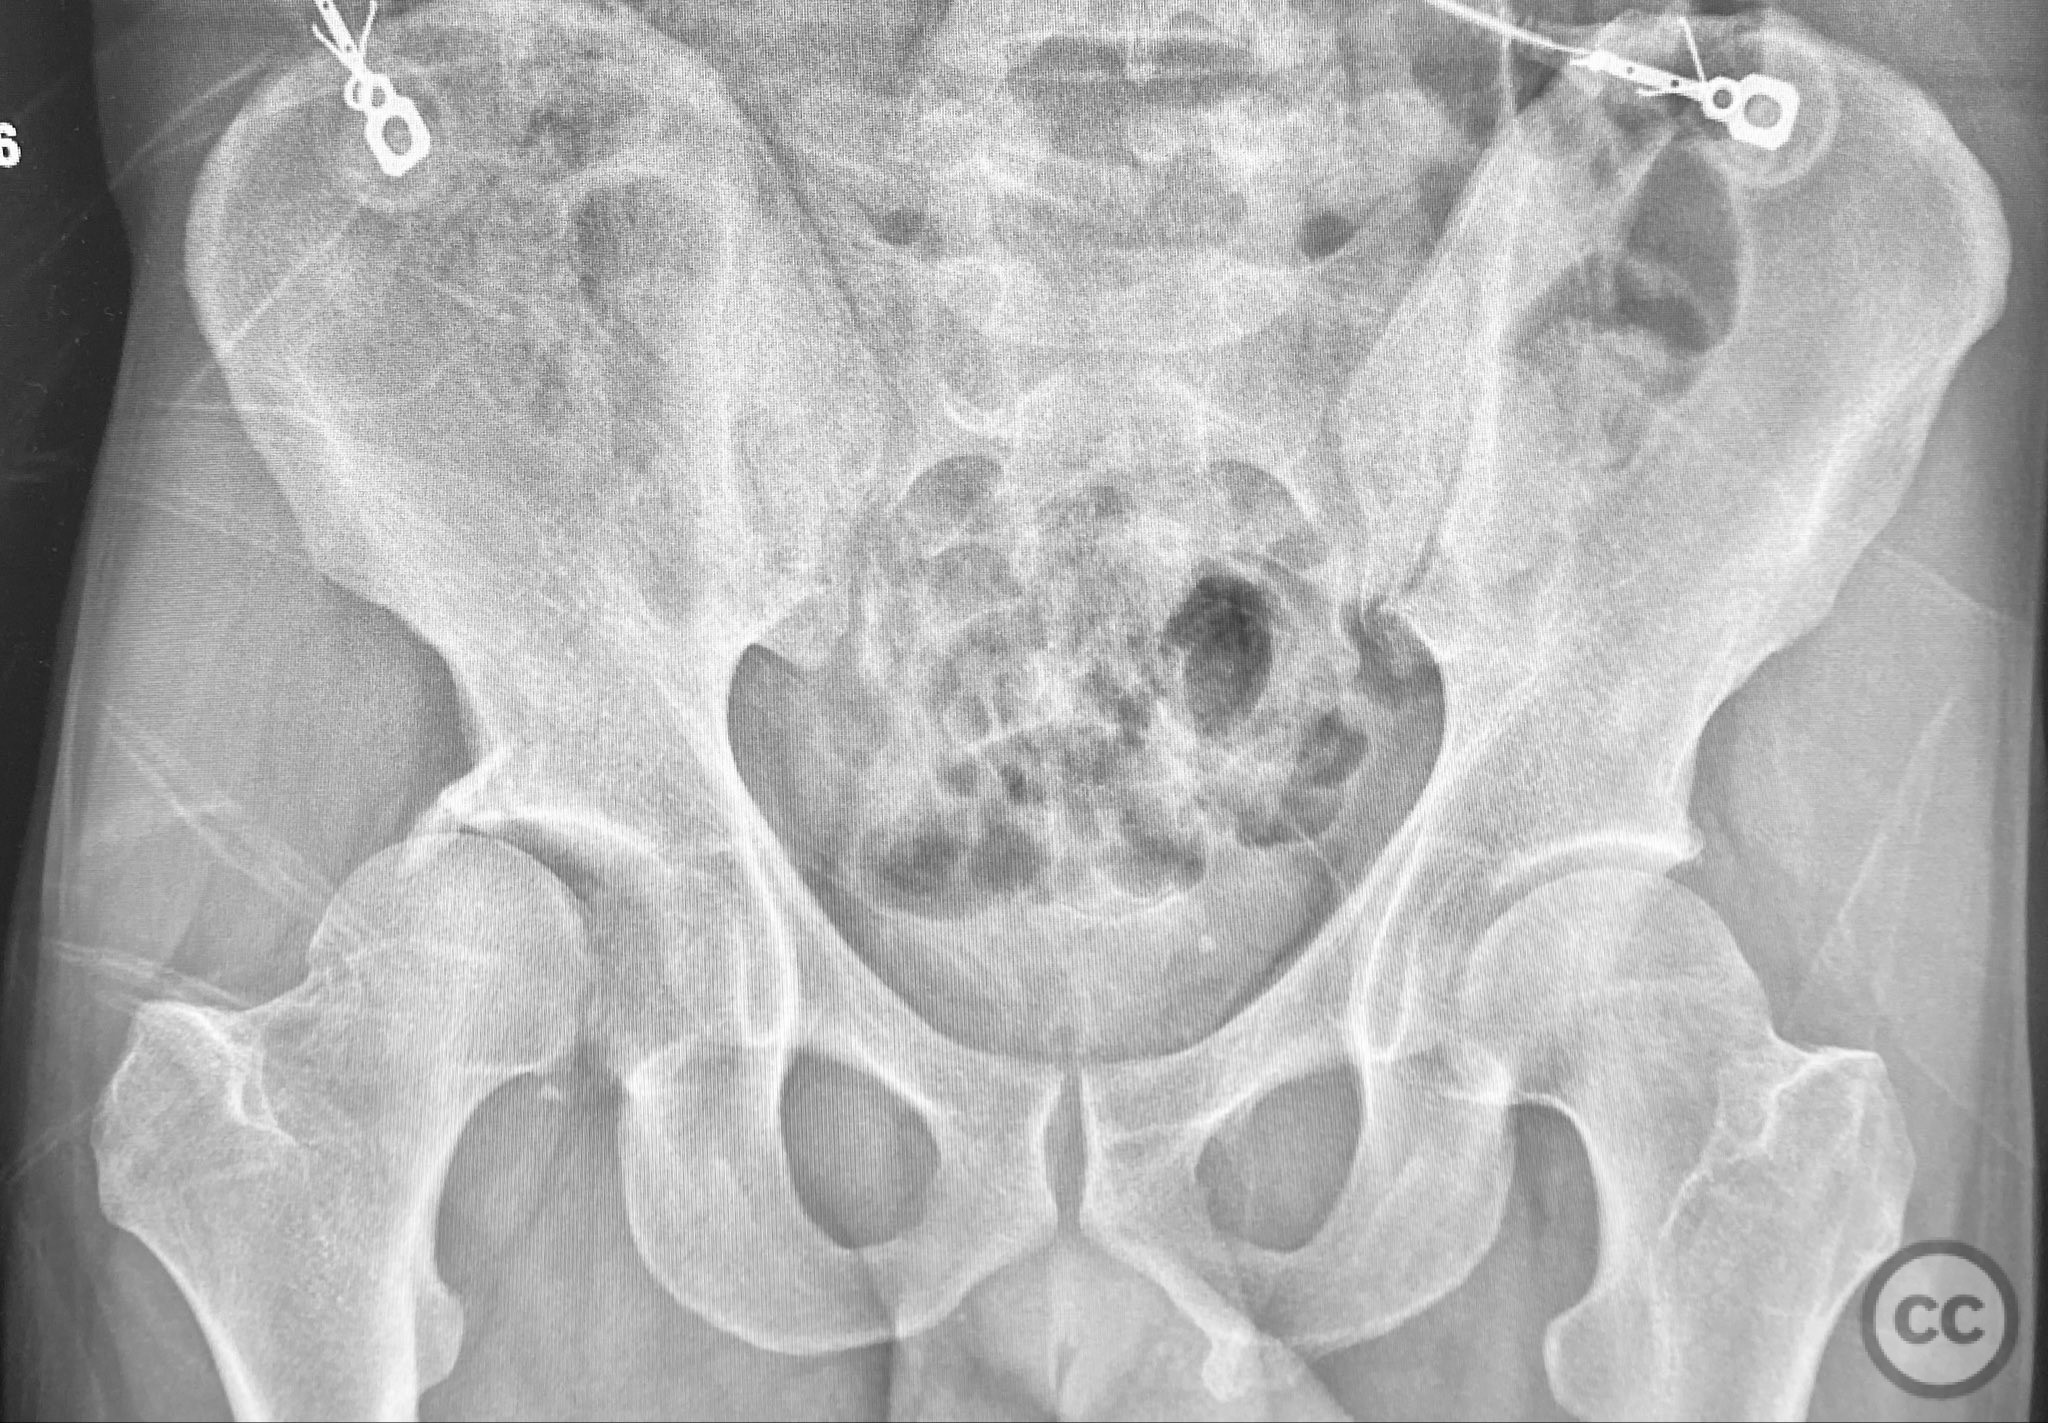

Posterior Wall Acetabular Fracture-Dislocation with Cranial Lateral Impaction and Failed Closed Reduction

Clinical and radiological findings:  A middle-aged patient sustained a posterior wall acetabular fracture-dislocation, as demonstrated on initial AP pelvic radiograph. The film revealed a sizeable posterior wall fragment, cranial lateral impaction of the acetabular dome, and subtle deformation of the femoral head contour. Neurovascular examination was performed, including assessment of distal pulses and sciatic nerve function. The ipsilateral knee and anterior chest were examined for associated injuries (including possible knee ligamentous injury and thoracic trauma). An initial attempt at closed reduction under sedation was unsuccessful.